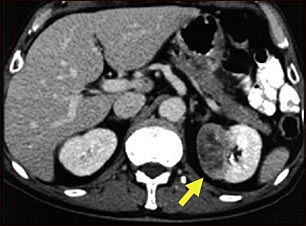

TC de tumor del riñón

Esta TC del abdomen muestra un tumor en el riñón izquierdo, llamado hipernefroma o carcinoma de células renales, ubicado en el lado inferior derecho de la imagen.